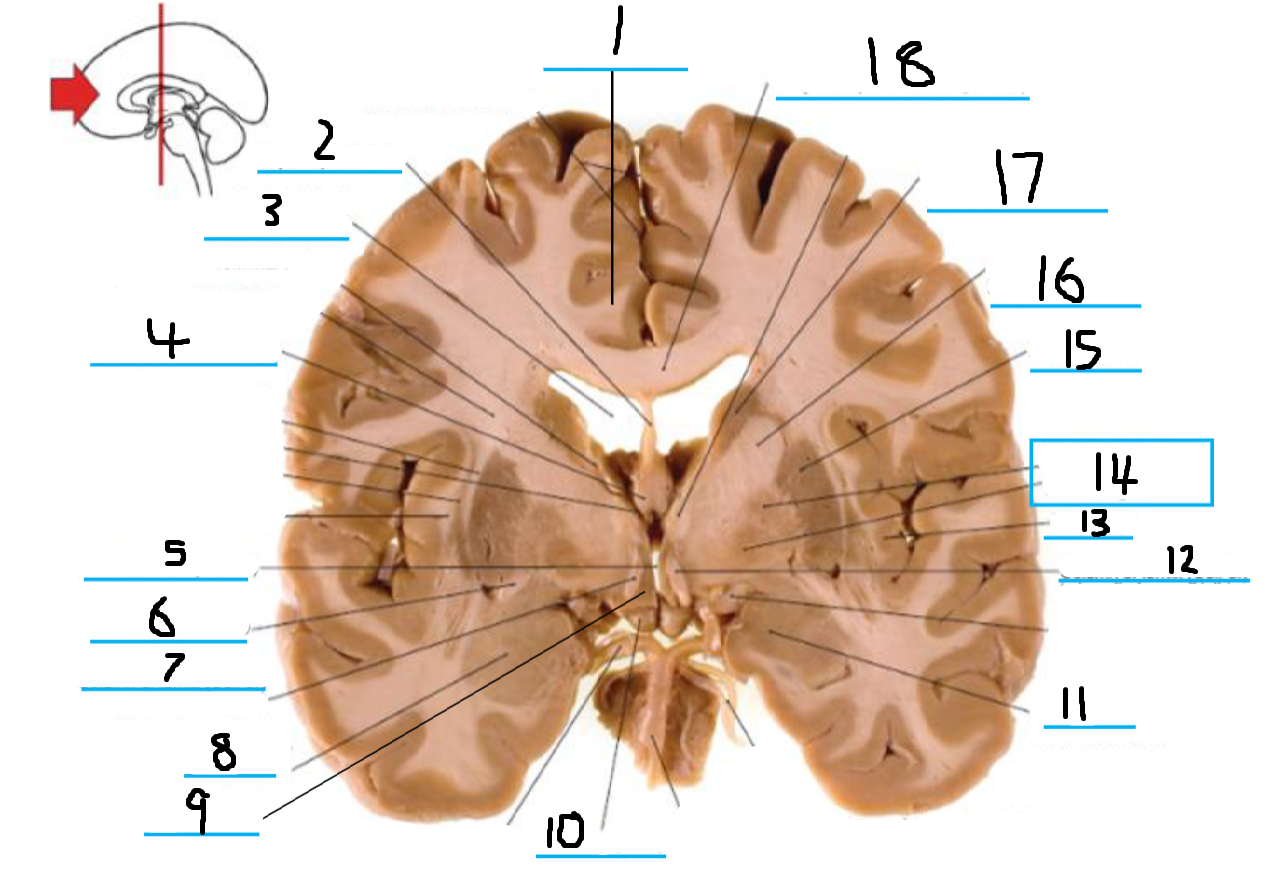

#1 is the:

Corpus Callosum

#2 is the:

Septum Pellucidum

#3 is the:

Lateral Ventricle

#4 and #9 is the:

Globus Pallidus

#5 is the:

Insula

#6 and #8 is the:

Anterior Commissure

#7 is the:

Optic Chiasm

#10 is the:

Putamen

#11 is the:

Internal Capsule

#12 is the:

Caudate